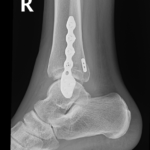

if the fracture is displaced, surgery may be needed to put the bone back into the correct position and fix the bone with Plates & screws or nails for adequate healing to occur.

- Ankle Fractures.